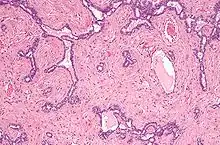

Micrografia do rete testis envolvida por seminoma. Mancha de H&E.